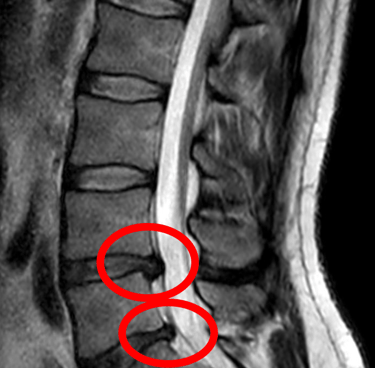

¿Qué es un Disco Herniado?

Un disco herniado ocurre cuando uno de los discos intervertebrales de tu columna se desplaza de su lugar o se rompe, presionando los nervios cercanos. Esto puede provocar dolor intenso, adormecimiento o hormigueo, especialmente en la espalda, cuello, brazos o piernas. Ya sea causado por una lesión, mala postura o el desgaste natural del envejecimiento, este problema común puede afectar significativamente tu calidad de vida.